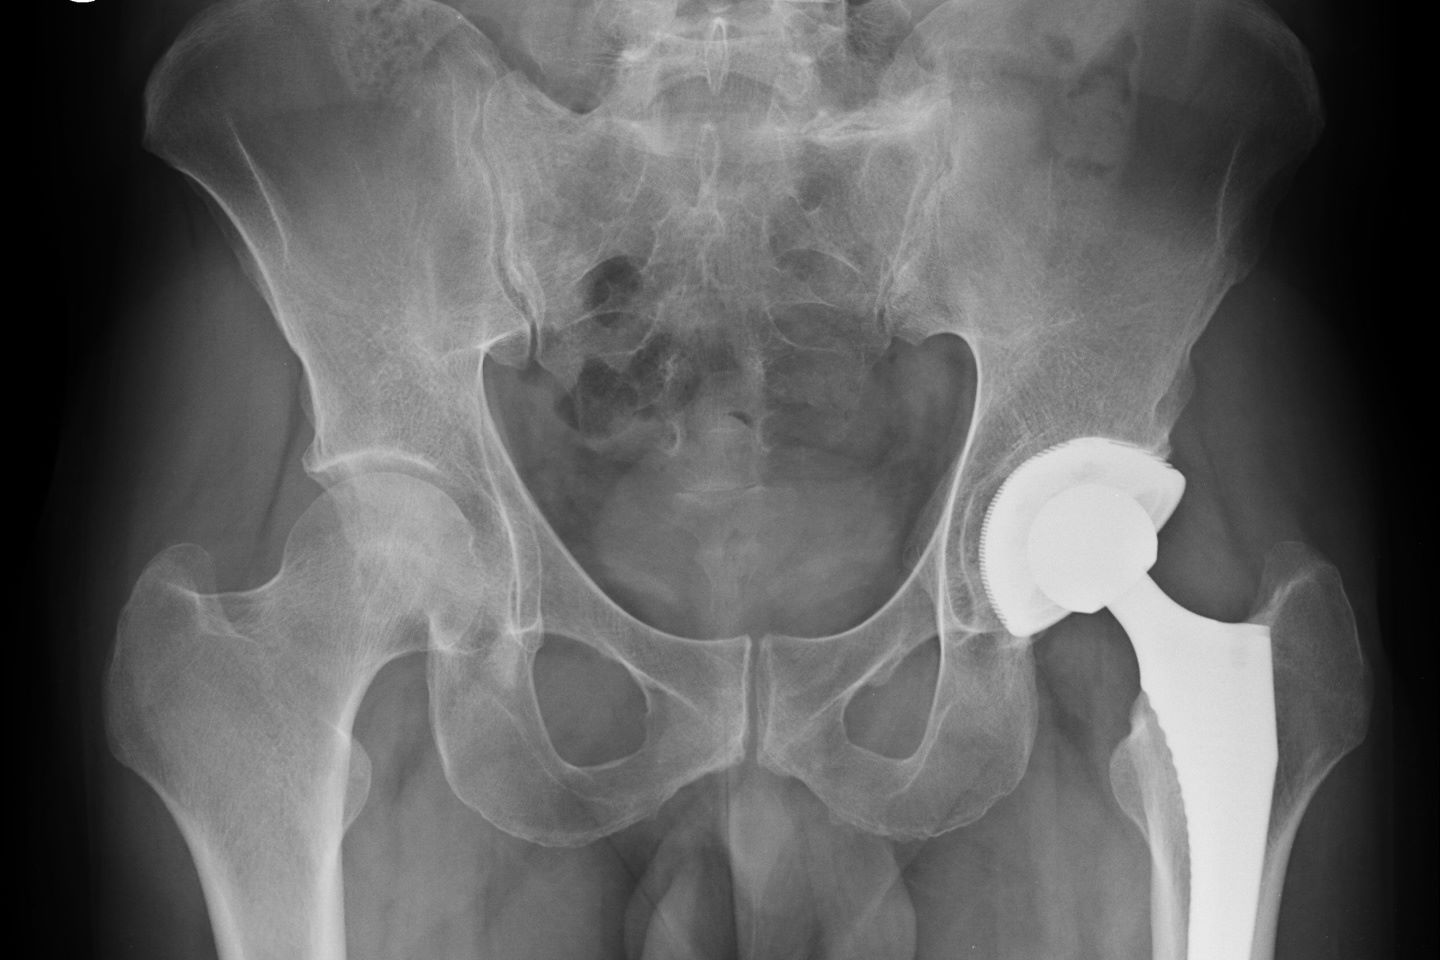

U stručnoj literaturi, kao i u medicinskoj dokumentaciji, nailazimo i na drugu terminologiju, poput endoproteza, artroplastika ili protetički implantat. Postupak obuhvaća odstranjenje oštećenih dijelova zgloba i ugradnju zamjenskih, to jest ugrađuje se novo zglobno tijelo s novim zglobnim površinama načinjenim od modernih umjetnih materijala.

Danas postoji mnoštvo različitih endoproteza, kako kuka, tako i ostalih zamjenskih zglobova, koje su varijacije osnovnog koncepta, u želji da se postigne što bolja stabilnost, mogućnost opterećenja i trajnost umjetnog zgloba.

Cilj liječenja umjetnim zglobovima je smanjenje boli, povećanje pokretljivosti zgloba i nadomještanje funkcije postojećega oštećenog zgloba. Kad govorimo o indikacijama za kirurško liječenje zamjene zgloba, ograničit ćemo se na najčešće lokacije - zglob kuka i koljenski zglob.